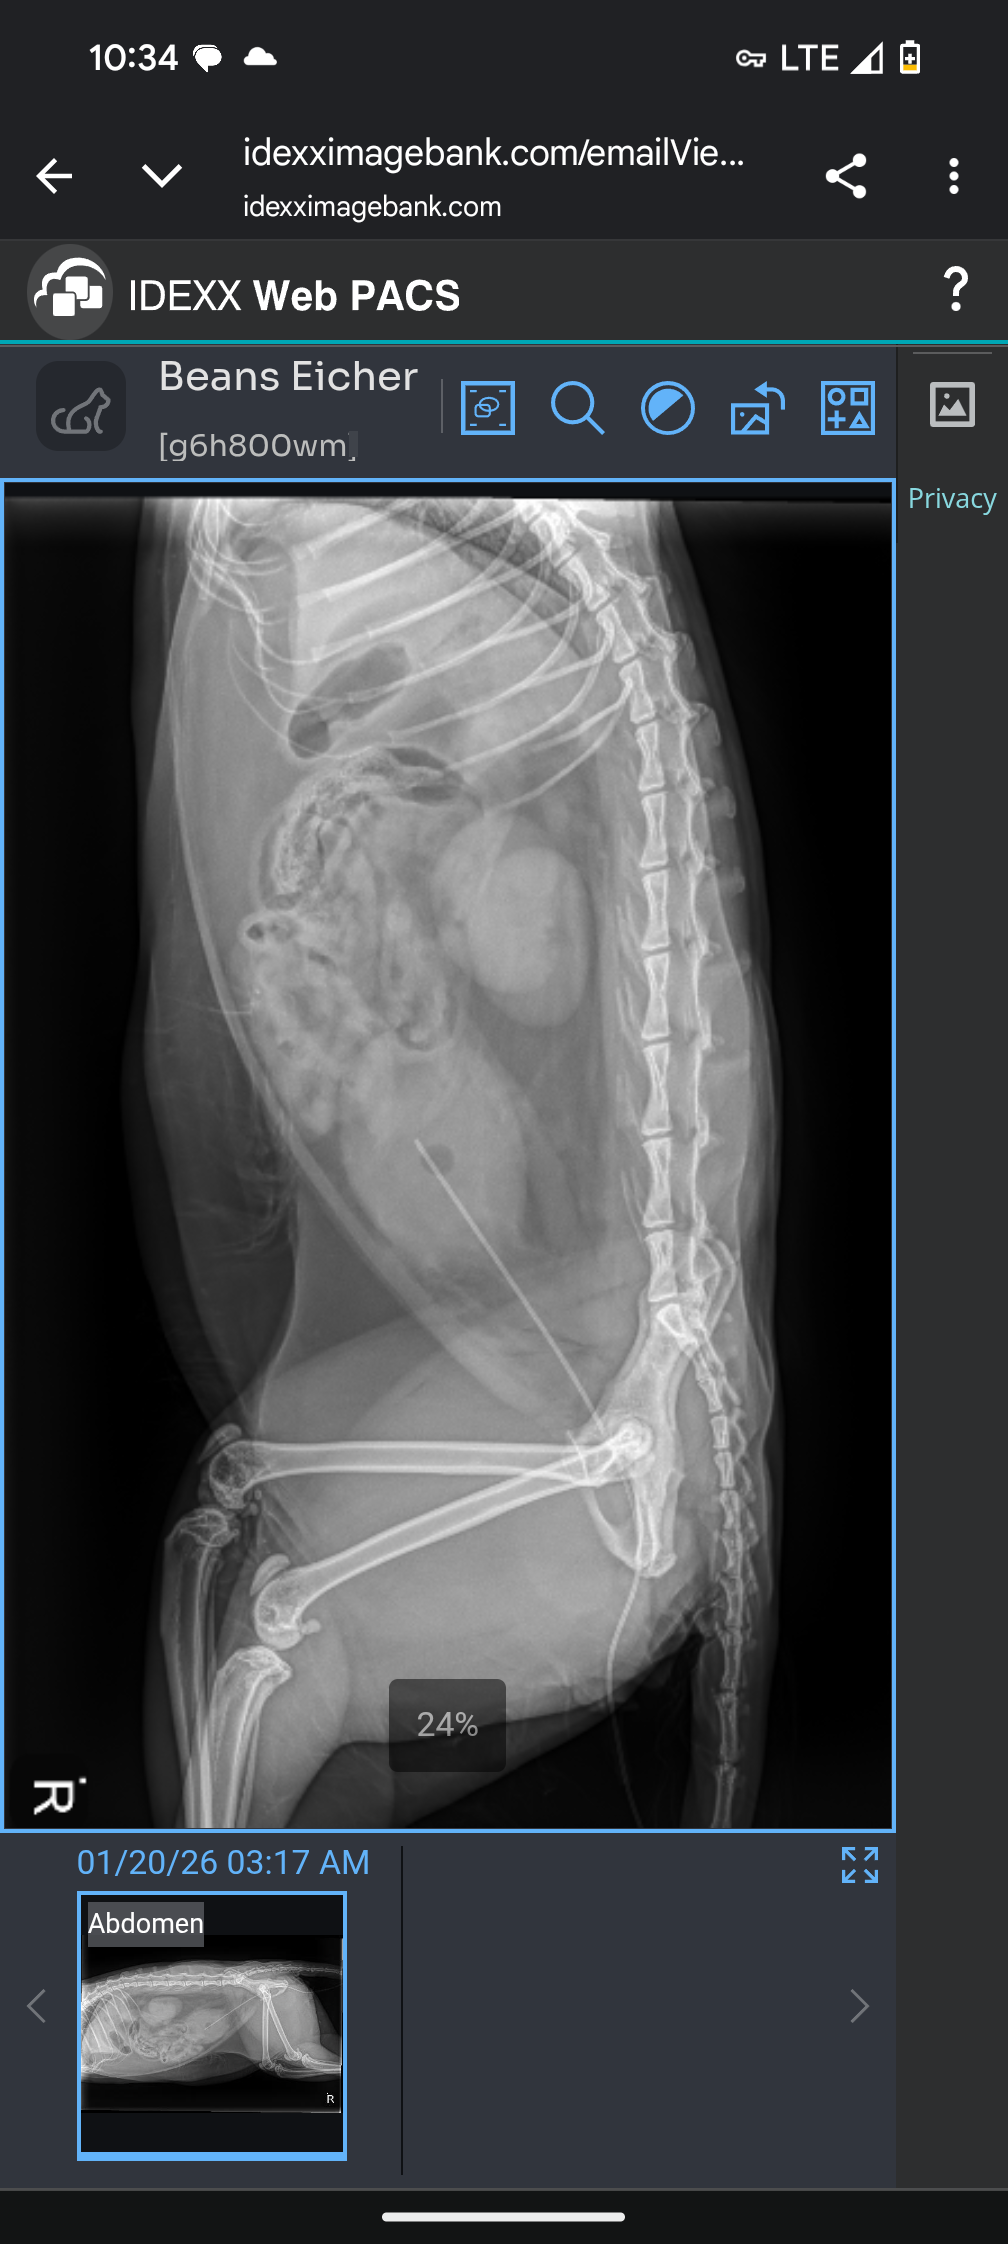

Hi there, my name is Lauren and this GoFundMe is for my baby boy, Beans. We had a sudden emergency vet visit come up where Beans has a blocked urethra, crystals in his bladder, possible stones, and at this point, his kidney values are six times the amount that they're supposed to be.

I'm not the kind of person to ask for help, but I'm asking for Beans. Currently, he is at VEG in East Lib for 24-hour observation. He had a kitty catheter put in and had his bladder drained. Unfortunately, his kidney values are high and that's why he's still in observation.